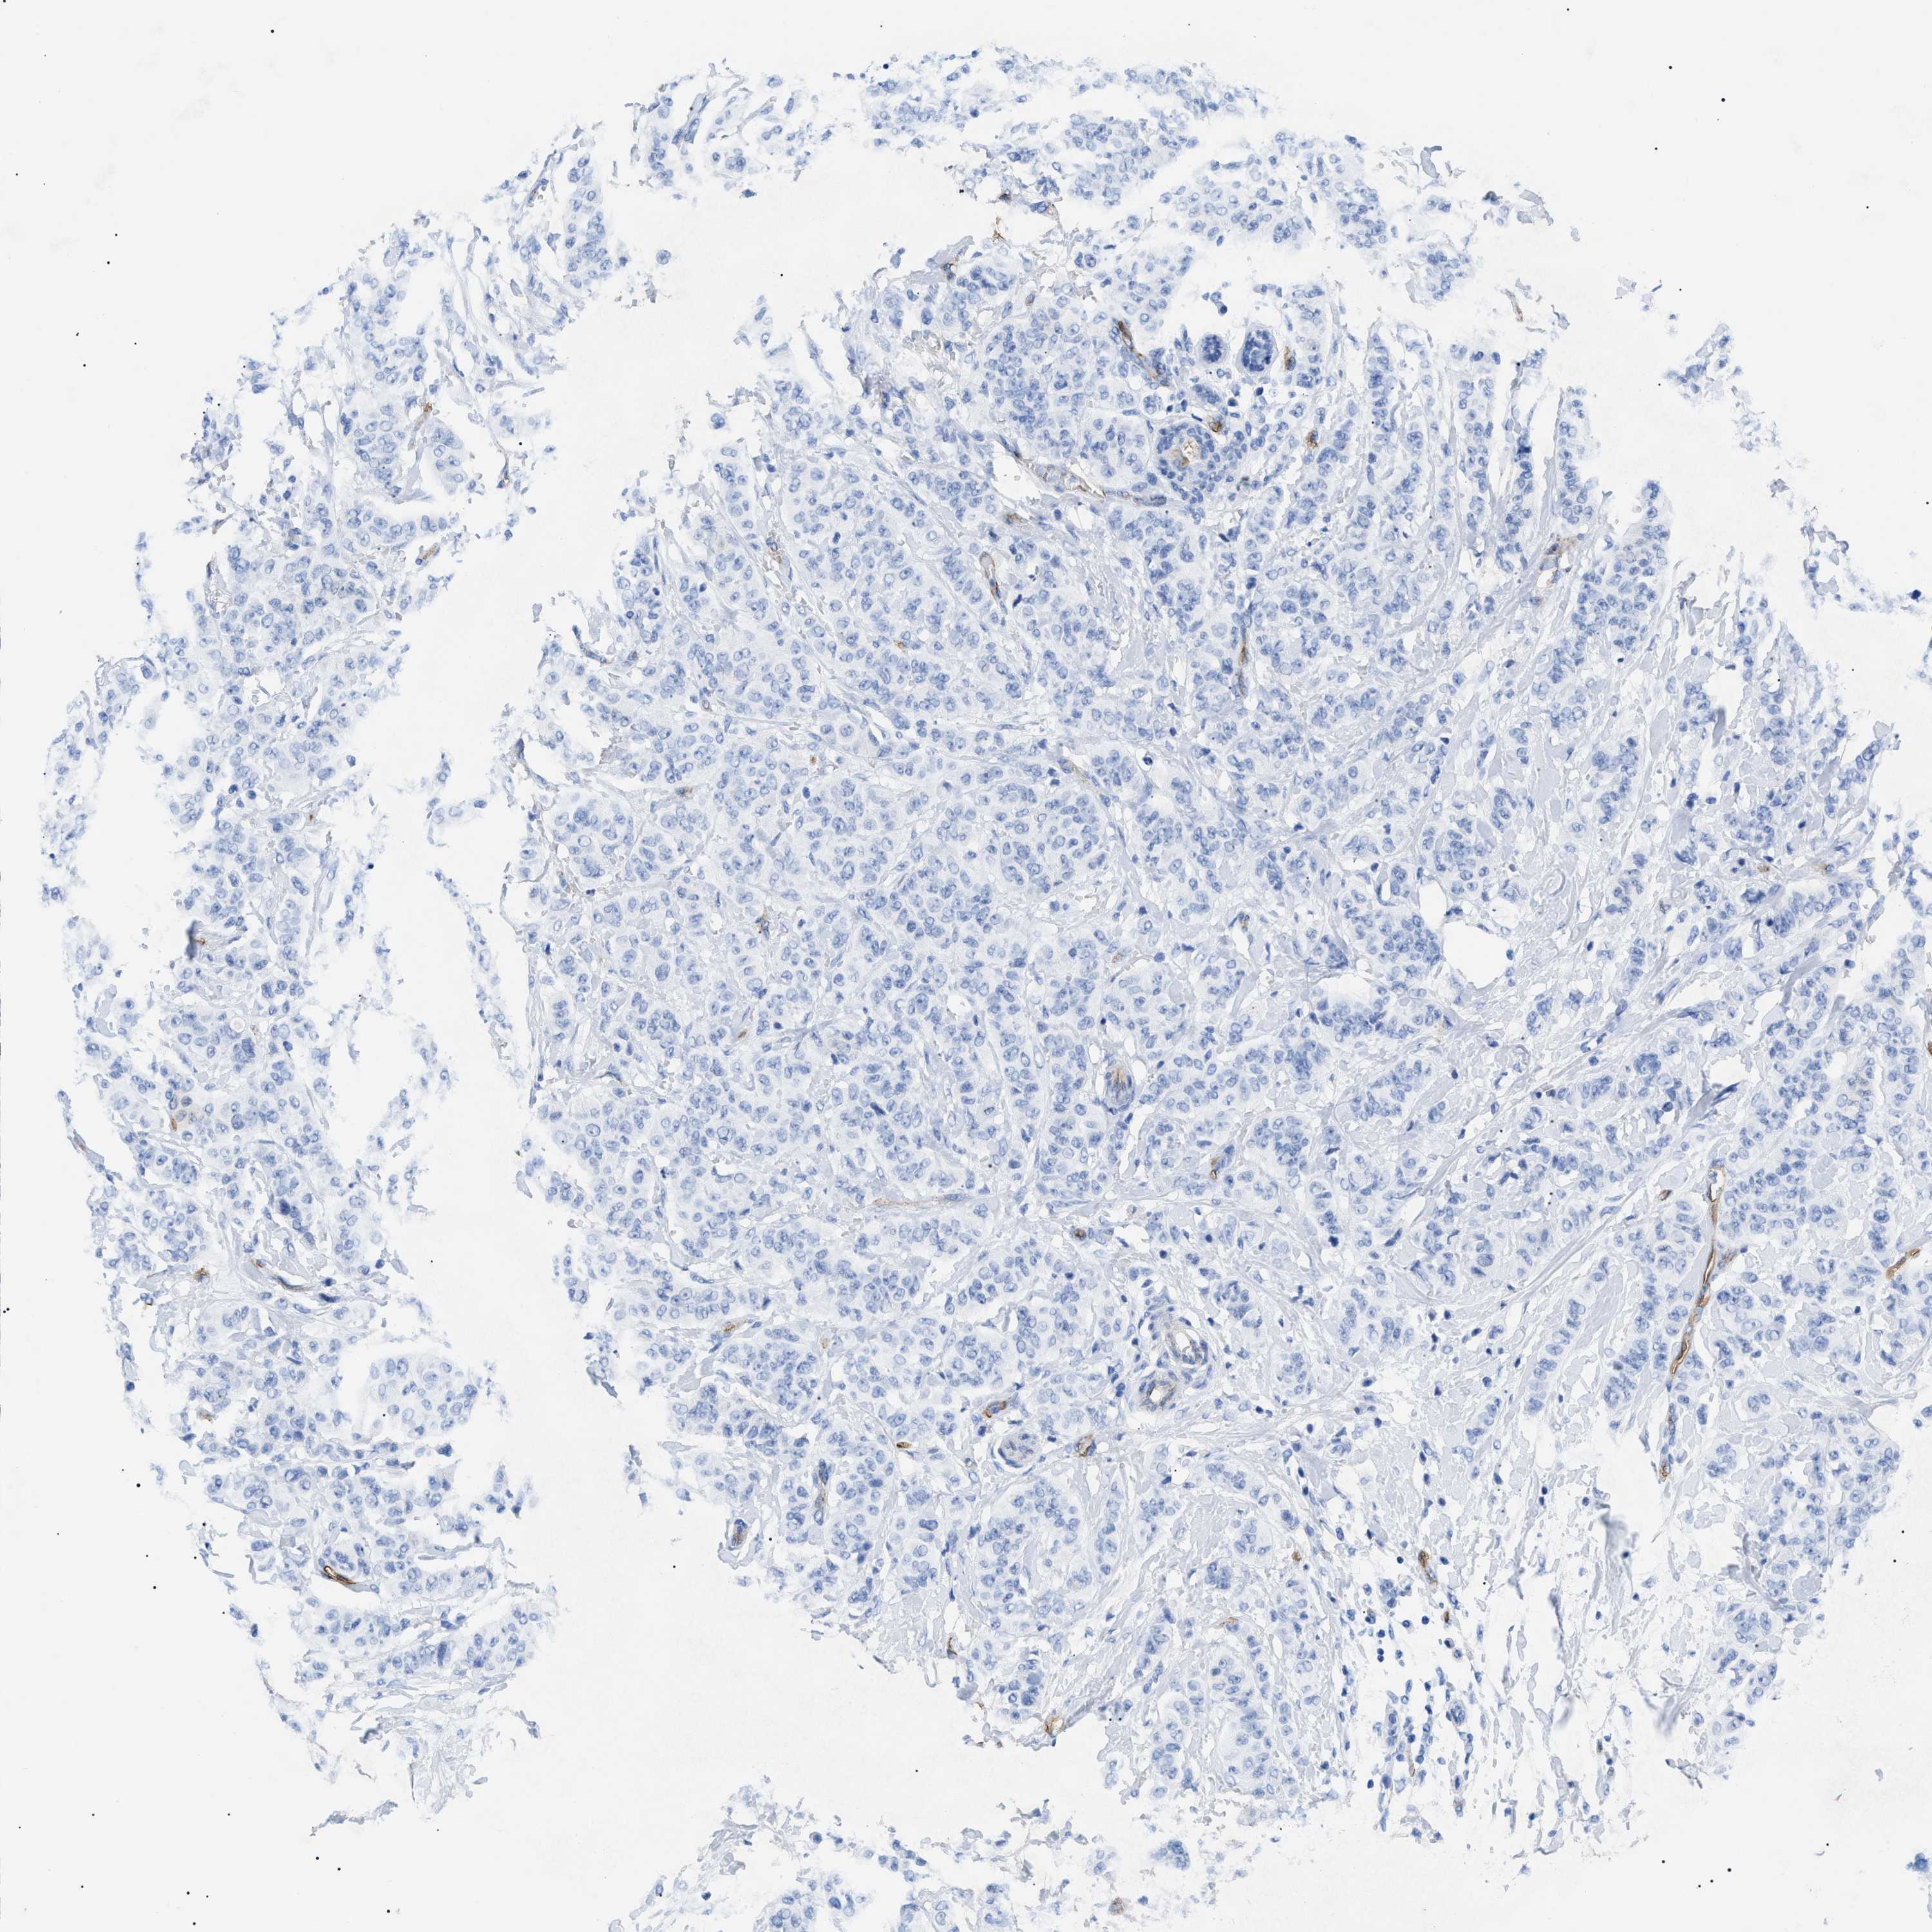

CANCER BREAST CANCER Show tissue menu

BRCA TCGA BRCA VALIDATION PROTEIN EXPRESSION